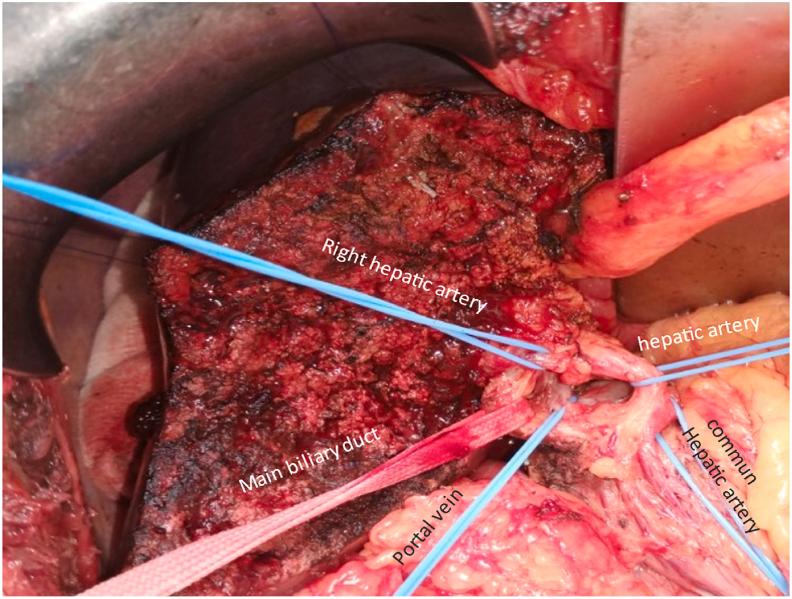

We present a 70-year-old woman, with no family or personal history, who was complaining of pain in the right hypochondrium and an altered general well-being, with no other clinical abnormalities.The imaging including abdominal sonography, CT scan, and MRI concluded at a budding lesion formed in the gallbladder wall which measured 65 × 15mm.Cancer of the gallbladder was suspected and the patient was operated. A resection of segment s4b and 5 of the liver was performed with lymphadenectomy. The post-operative clinical course was uneventful.The diagnosis of cystadenocarcinoma of the gallbladder was confirmed on an anatomopathological exam of the specimen.

我们报告一名70岁女性,无家族史或个人史,主诉右季肋部疼痛且全身状况不佳,无其他临床异常。包括腹部超声、CT扫描和MRI在内的影像学检查发现胆囊壁上有一个大小为65×15mm的芽状病变。怀疑为胆囊癌,患者接受了手术。进行了肝S4b和S5段切除及淋巴结清扫术。术后临床过程平稳。标本的解剖病理学检查证实为胆囊囊腺癌。